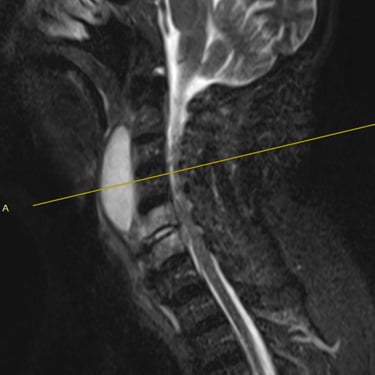

Discitis Cervical con Absceso: Descompresión Cervical y Artrodesis

La discitis cervical con absceso es una infección grave de la columna que puede comprometer el disco intervertebral, los cuerpos vertebrales y las estructuras neurológicas, generando dolor cervical intenso, fiebre y déficit neurológico progresivo. Cuando existe compresión medular o inestabilidad, el tratamiento quirúrgico mediante descompresión cervical y artrodesis es fundamental. Este procedimiento permite drenar el absceso, liberar la médula espinal y estabilizar el segmento afectado, favoreciendo el control de la infección y la recuperación neurológica. El manejo oportuno y multidisciplinario es clave para mejorar el pronóstico del paciente.